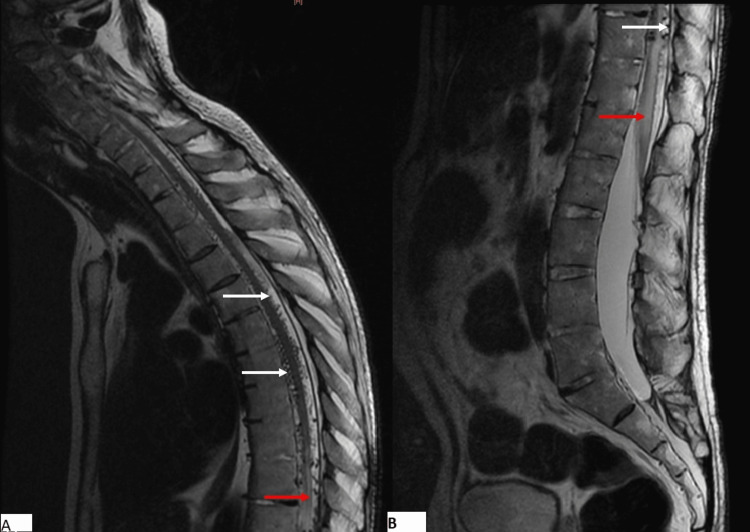

A 65-year-old male, with a remarkable medical history involving poorly managed diabetes mellitus and hypertension, was admitted for the evaluation of progressive paraplegia for 18 months. This was associated with tingling in the lower extremities. On admission, his blood pressure was 170/90 mmHg, and his heart rate was normal at 75 pulses per minute. He was alert and oriented but had difficulty standing up. Physical examination revealed a complete impairment of muscle function in both lower extremities. Osteotendinous reflexes were polykinetic and the Babinski sign was positive in both feet. Sensory perceptions of pain, vibration, and touch were impaired. Based on these findings, we graded his condition as Frankel grade B. We performed an MRI of the spine and brain, which revealed no compression but a tumefied thoracolumbar spinal cord, revealing a high signal intensity in T2-weighted images (Figure 1) and low signal intensity in T1-weighted images. MRI findings also showed prominent serpentine T2 flow voids in the intradural space corresponding to dilated perimedullary veins (Figure 1).

Figure 1. Sagittal T2WI of the cervicothoracic (A) and lumbar (B) spine showing hyperintense enlarged spinal cord and conus medullaris (red arrow), associated with flow void (white arrows) corresponding to enlarged veins.